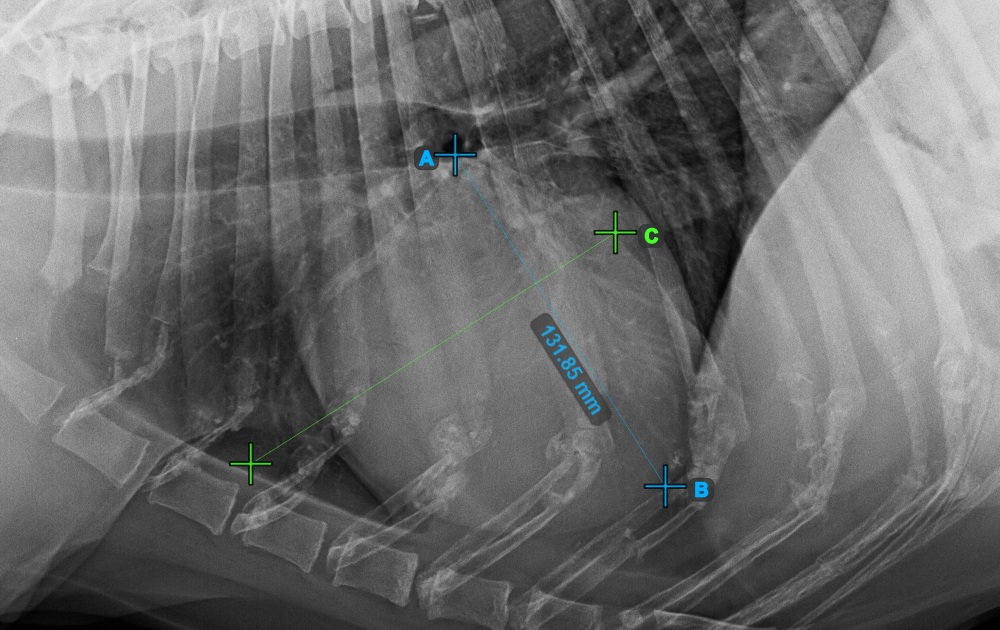

Continue the measurement by marking the widest right (cranial) point of the short axis of the heart.

The image below represents a typical placement of the most cranial point on the short axis of the heart.